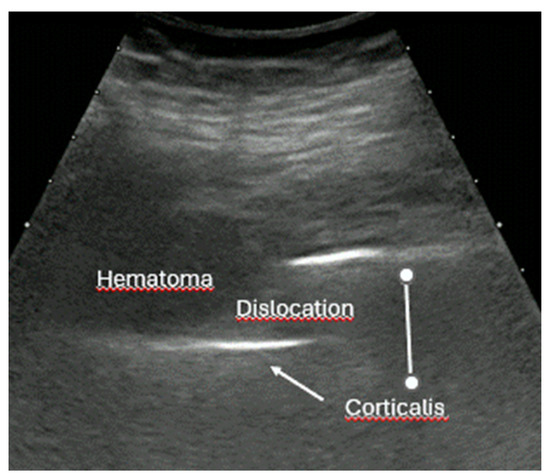

- Dislocation: misalignment of bone fragments, visible as separation or shift from their normal anatomical position.

- Local hematoma or soft tissue edema: fluid collections or increased echogenicity near the fracture site indicating bleeding and inflammation.

- Quick exclusion of fractures in shoulder dislocations for timely reduction (Figure 13).

- Recommendation 6: Ultrasound should be integrated into the assessment and management of shoulder injuries, including proximal humerus fractures, shoulder dislocations, and post-relocation maneuvers, both prehospitally, in emergency departments, and other acute care settings.

- Example: Suspected left shoulder dislocation